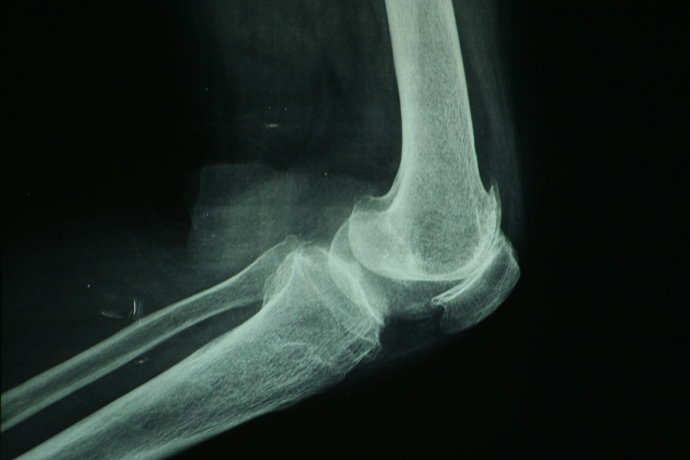

退行性膝关节炎辅助检查

X片检查

实验室检查:1、关节液为非炎性,白细胞一般不超过1000个;2、血沉(ESR)正常;3、抗“O”及类风湿因子阴性